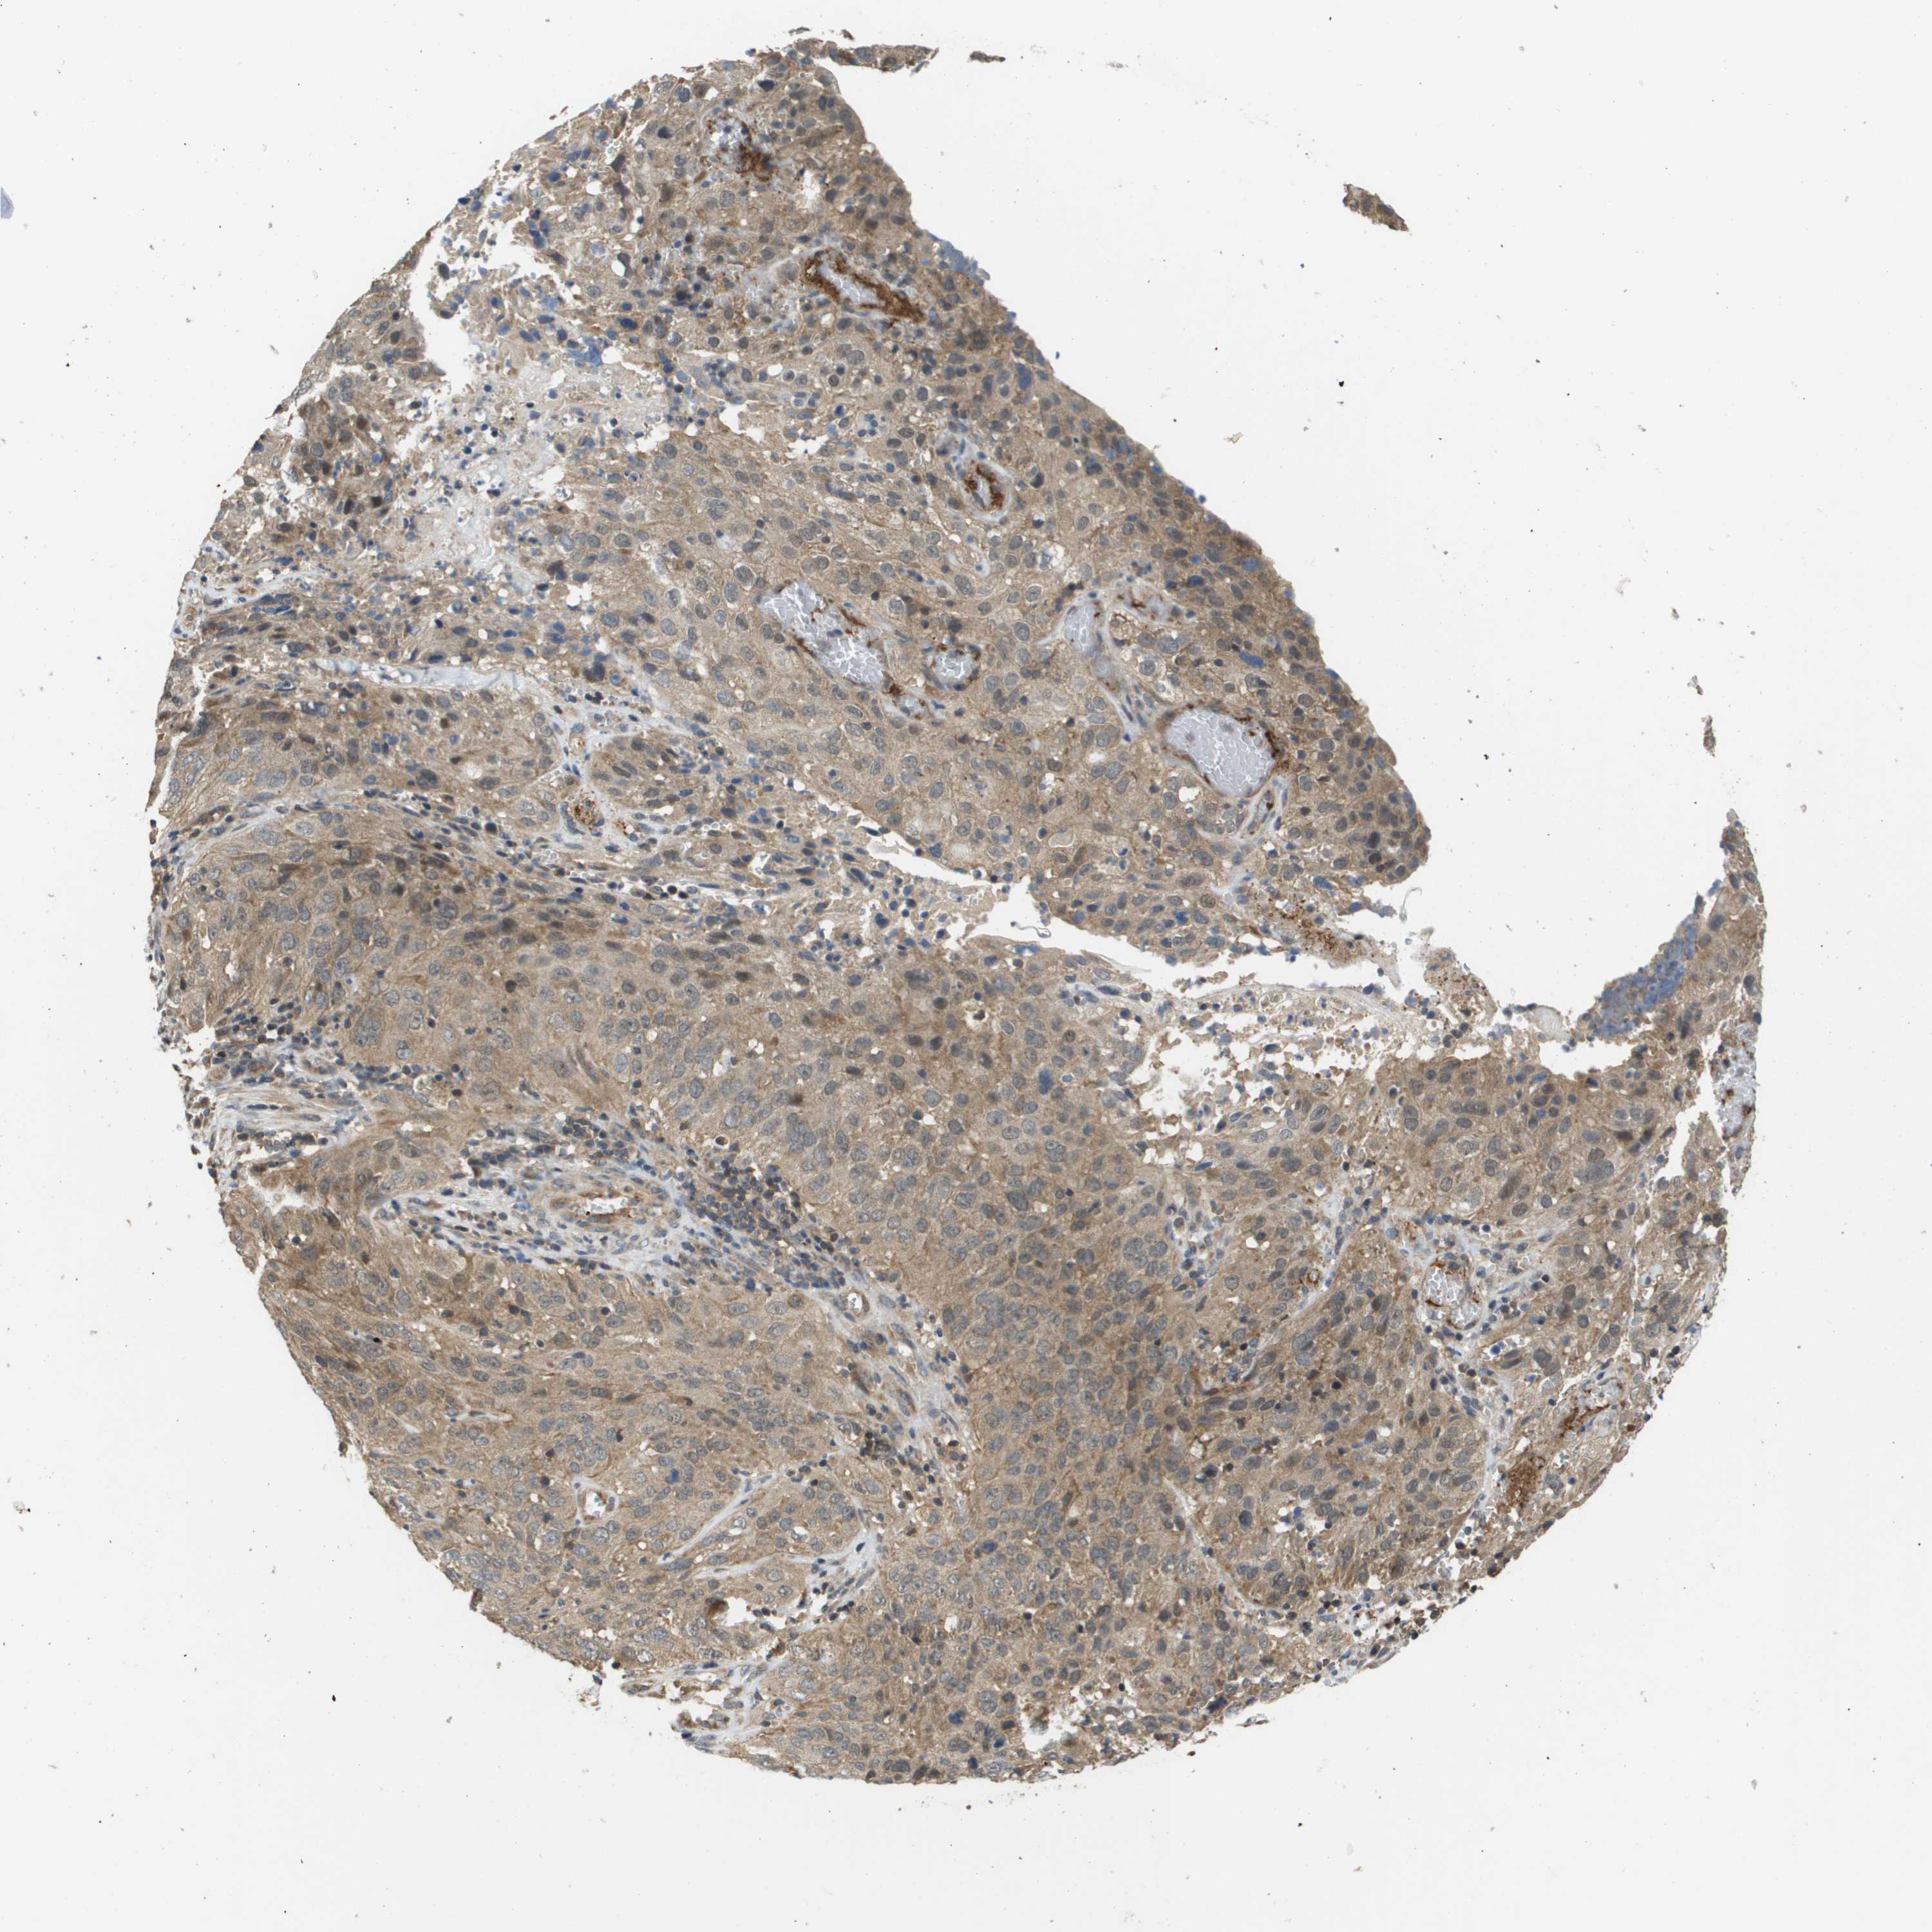

CERVICAL CANCER - Protein expressioni

A mouse-over function shows sample information and annotation data. Click on an image to view it in a full screen mode. Samples can be filtered based on level of antibody staining by selecting one or several of the following categories: high, medium, low and not detected. The assay and annotation is described here.

Note that samples used for immunohistochemistry by the Human Protein Atlas do not correspond to samples in the TCGA dataset.

Antibody stainingi

Antibody staining in the annotated cell types in the current human tissue is reported as not detected, low, medium, or high, based on conventional immunohistochemistry profiling in selected tissues. This score is based on the combination of the staining intensity and fraction of stained cells.

Each image is clickable and will lead to virtual microscopy that enables deeper exploration of all samples and also displays staining intensity scores, fraction scores and subcellular localization as well as patient and tissue information for each sample.

Antibody CAB017036

Staining

High

Medium

Low

Not detected

Intensity

Strong

Moderate

Weak

Negative

Quantity

>75%

75%-25%

<25%

None

Location

Nuclear

Cytoplasmic/membranous

Cytoplasmic/membranous,nuclear

Squamous cell carcinoma, NOS

Adenocarcinoma, NOS